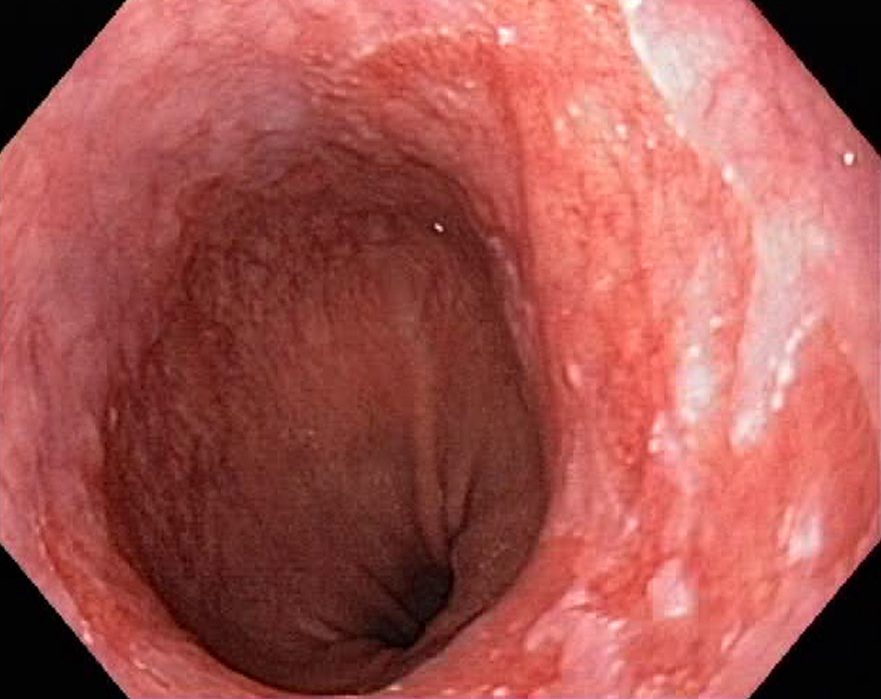

Barrets Oesophagus (NBI, Narrow Band Imaging)